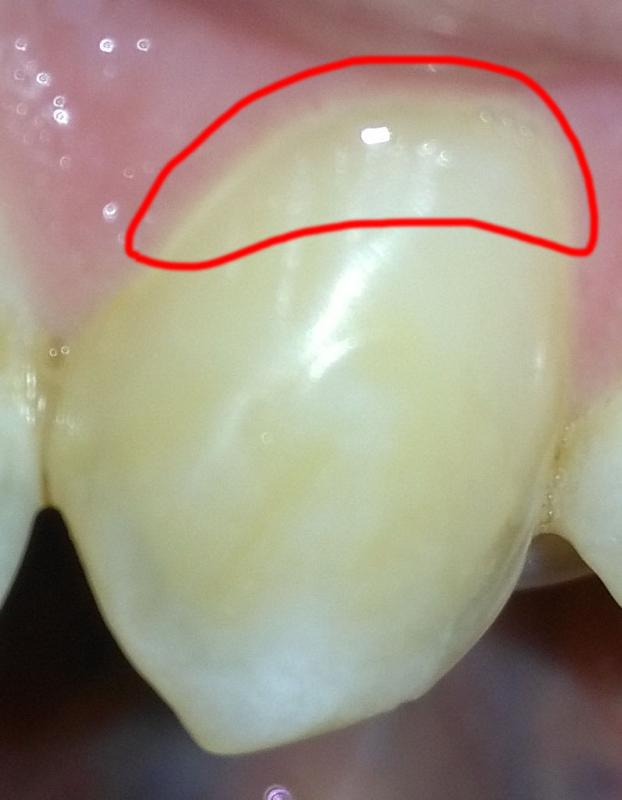

Воля Опубликовано 28 мая, 2018 Автор Поделиться Опубликовано 28 мая, 2018 (изменено) Но это фотка нынешней пломбы. Фоток, когда мне с клыков соскребли что-то белое типа каши нет т.к. тогда даже смартфонов не было, чтобы снять. Поэтому пытаюсь описывать словами то, что видел своими глазами. Фото под спойлером из этой темы на этом же форуме Боль при надавливании на пломбу Изменено 28 мая, 2018 пользователем Воля Ссылка на комментарий